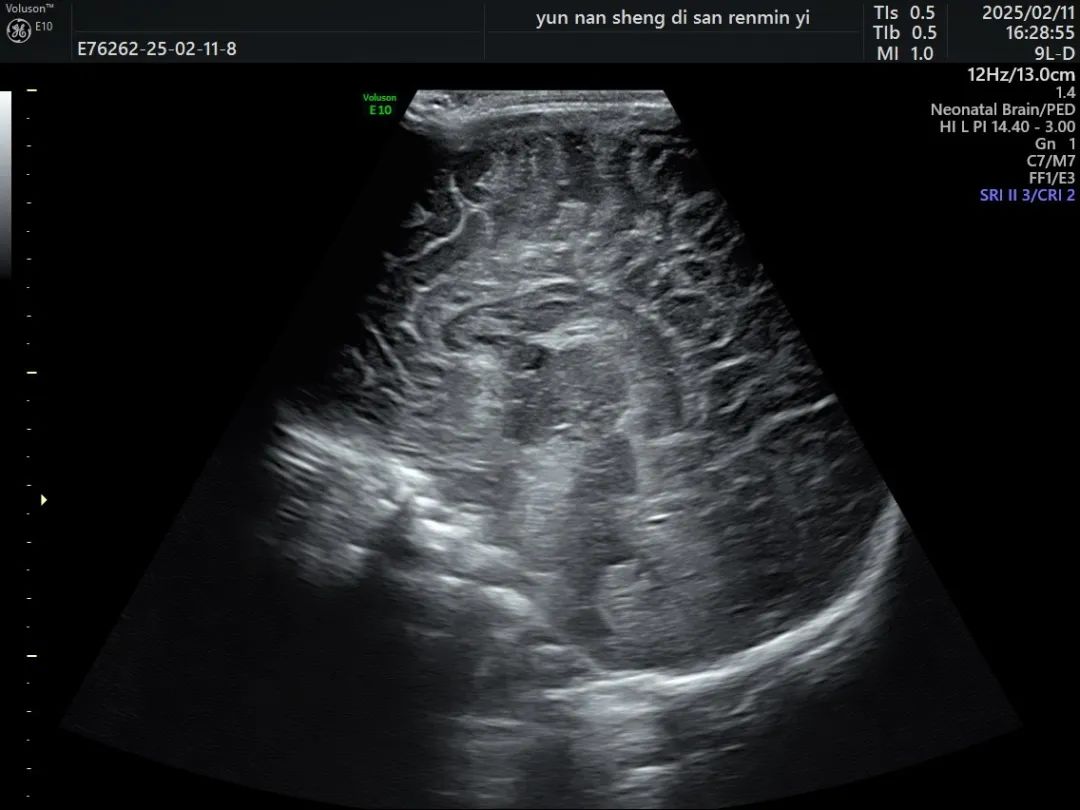

小儿颅脑超声检查是通过超声仪器,利用尚未闭合的囟门(如前囟、乳突囟、后囟等)作为声窗,对颅内结构进行扫描和观察。这种方法可以清晰地显示大脑、小脑、脑干等重要结构,以及颅内血管的情况,是一项可以与头颅核磁共振相媲美的检查方式。

超声检查能够帮助医生早期发现颅内出血、脑积水、脑损伤、感染等疾病,为临床治疗提供重要依据。

(颅脑超声图)